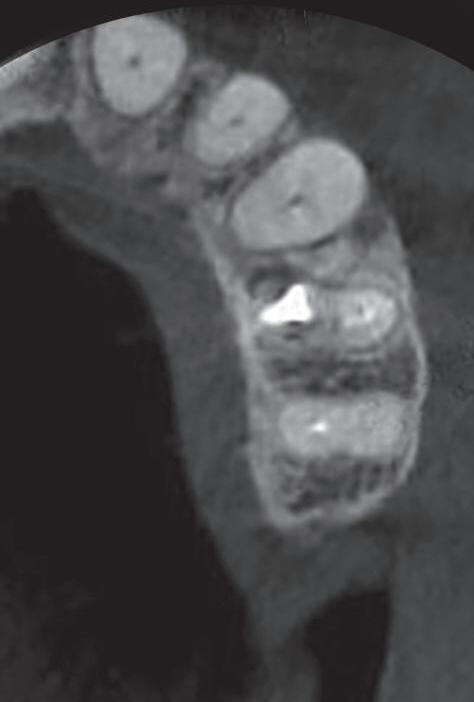

Fig. 19-1. Paciente idoso submetido a tratamento endodôntico (dente 25). (a) Canais atresiados (visualizados na radiografia periapical.) ( bliteração da entrada do canal vestibular. (d) Canal localizado e ampliado (uso de microscopia e ultrassom). ( a